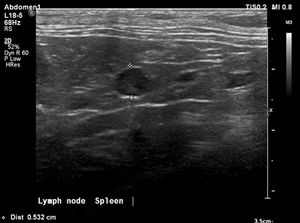

Dr. Janina Bartels provides the radiology perspective on this challenging oncology case.